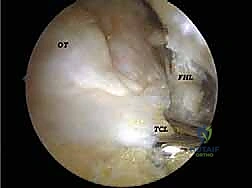

* تحرير وتنظيف وتر (FHL): إذا كان الوتر ملتهباً ومحاصراً، يتم قطع سقف النفق الليفي لتحريره، وإزالة الأنسجة الملتهبة (Tenosynovectomy) لضمان انزلاقه بحرية.

الخطوة 3: الاستكشاف البانورامي (Diagnostic Arthroscopy)

يتم إدخال كاميرا المنظار عالية الدقة (4K) عبر أحد المداخل، بينما تُستخدم الأدوات الجراحية الدقيقة في المدخل الآخر. تتيح الكاميرا للدكتور هطيف رؤية الهياكل الداخلية مكبرة عشرات المرات على شاشة عملاقة، مما يسمح بتقييم دقيق للمفاصل، الأوتار، والأربطة.

* استئصال العظم الزائد (Os Trigonum Excision): يتم فصل العظم الزائد بحذر عن الأنسجة المحيطة واستخراجه بالكامل، مما يزيل سبب الانحشار والألم فوراً.